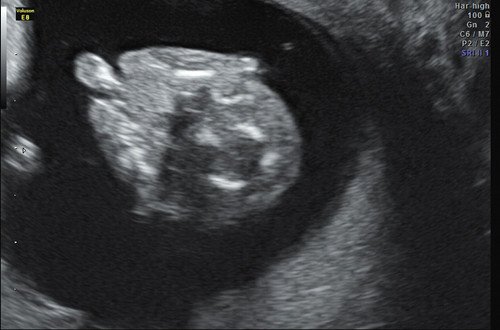

Пациентка Н. 28 лет. Беременность вторая, есть один здоровый ребенок. Женщина и муж соматически здоровы, брак неродственный. Обратилась в медико-генетическое отделение МОНИИАГ в 12,6 недели беременности с подозрением на ВПР лица у плода при проведении скринингового экспертного ультразвукового исследования в окружном кабинете. У плода выявлены: двусторонняя расщелина лица (рис. 7, 8), эктродактилия кистей (рис. 9, 10), односторонняя пиелоэктазия (рис. 11). Проведено медико-генетическое консультирование. Семья приняла решение прервать данную беременность с инвалидизирующими пороками развития. Окончательный диагноз: "синдром ЕЕС, аутосомно-доминантный тип наследования". Мутация de novo.

Рис. 7. Расщелина лица. 12,6 недели беременности.

Рис. 8. Расщелина лица. 12,6 недели беременности.